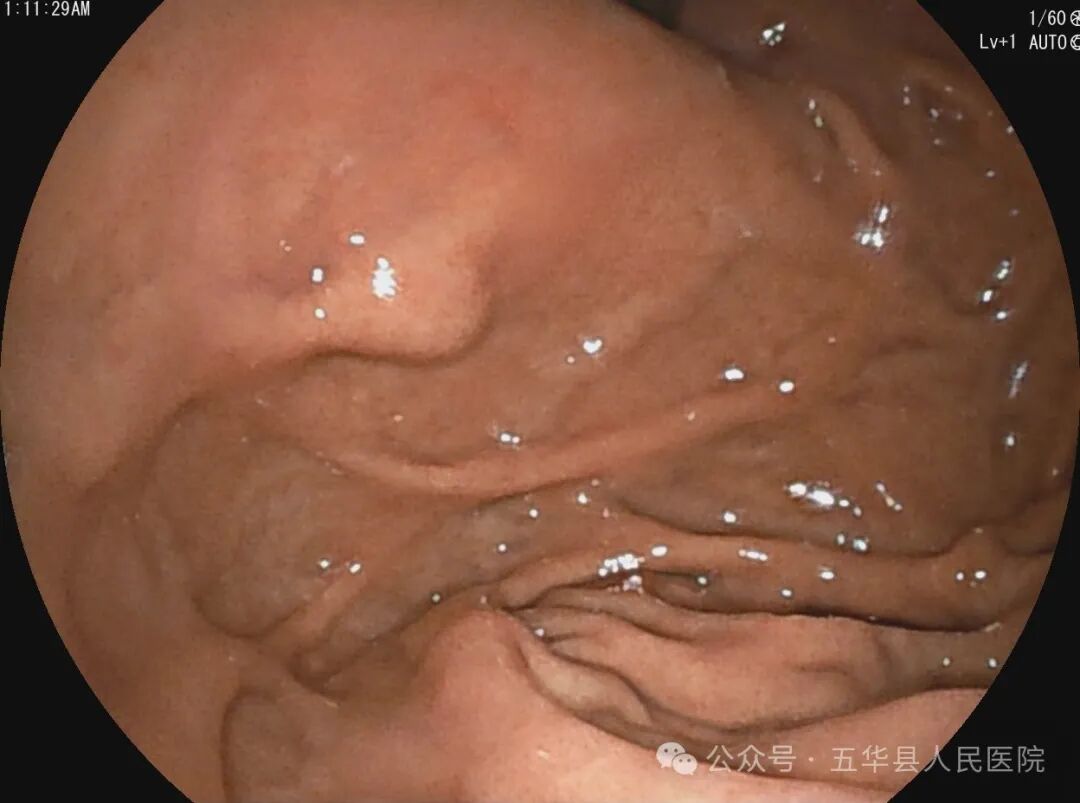

据悉,该患者为老年女性,长期上腹部不适,近期患者症状加重,来我院行胃镜检查发现胃底黏膜下隆起,胃多发息肉。胃黏膜下隆起可能是胃肿瘤如间质瘤、平滑肌瘤、神经内分泌瘤等,也可能是胃壁外血管或脏器压迹,需要行超声内镜检查加以鉴别,为下一步治疗奠定基础。既往我县无超声内镜设备及技术,此类患者需要前往市医院接受检查。我院超声内镜检查的成功开展,标志着五华县内镜诊疗进入新的发展阶段。

超声内镜是将微型高频超声探头安置在内镜顶端,就像是给内镜开启了“透视”功能。在内镜直接观察消化道黏膜病变的基础上,利用超声实时扫描,可获得检查脏器及周围邻近脏器的超声图像,“透视”人体管腔的层次结构、病变起源和浸润深度,甚至是周围邻近脏器的组织结构也一览无遗,真正意义上实现了消化系统疑难疾病的精准诊断。